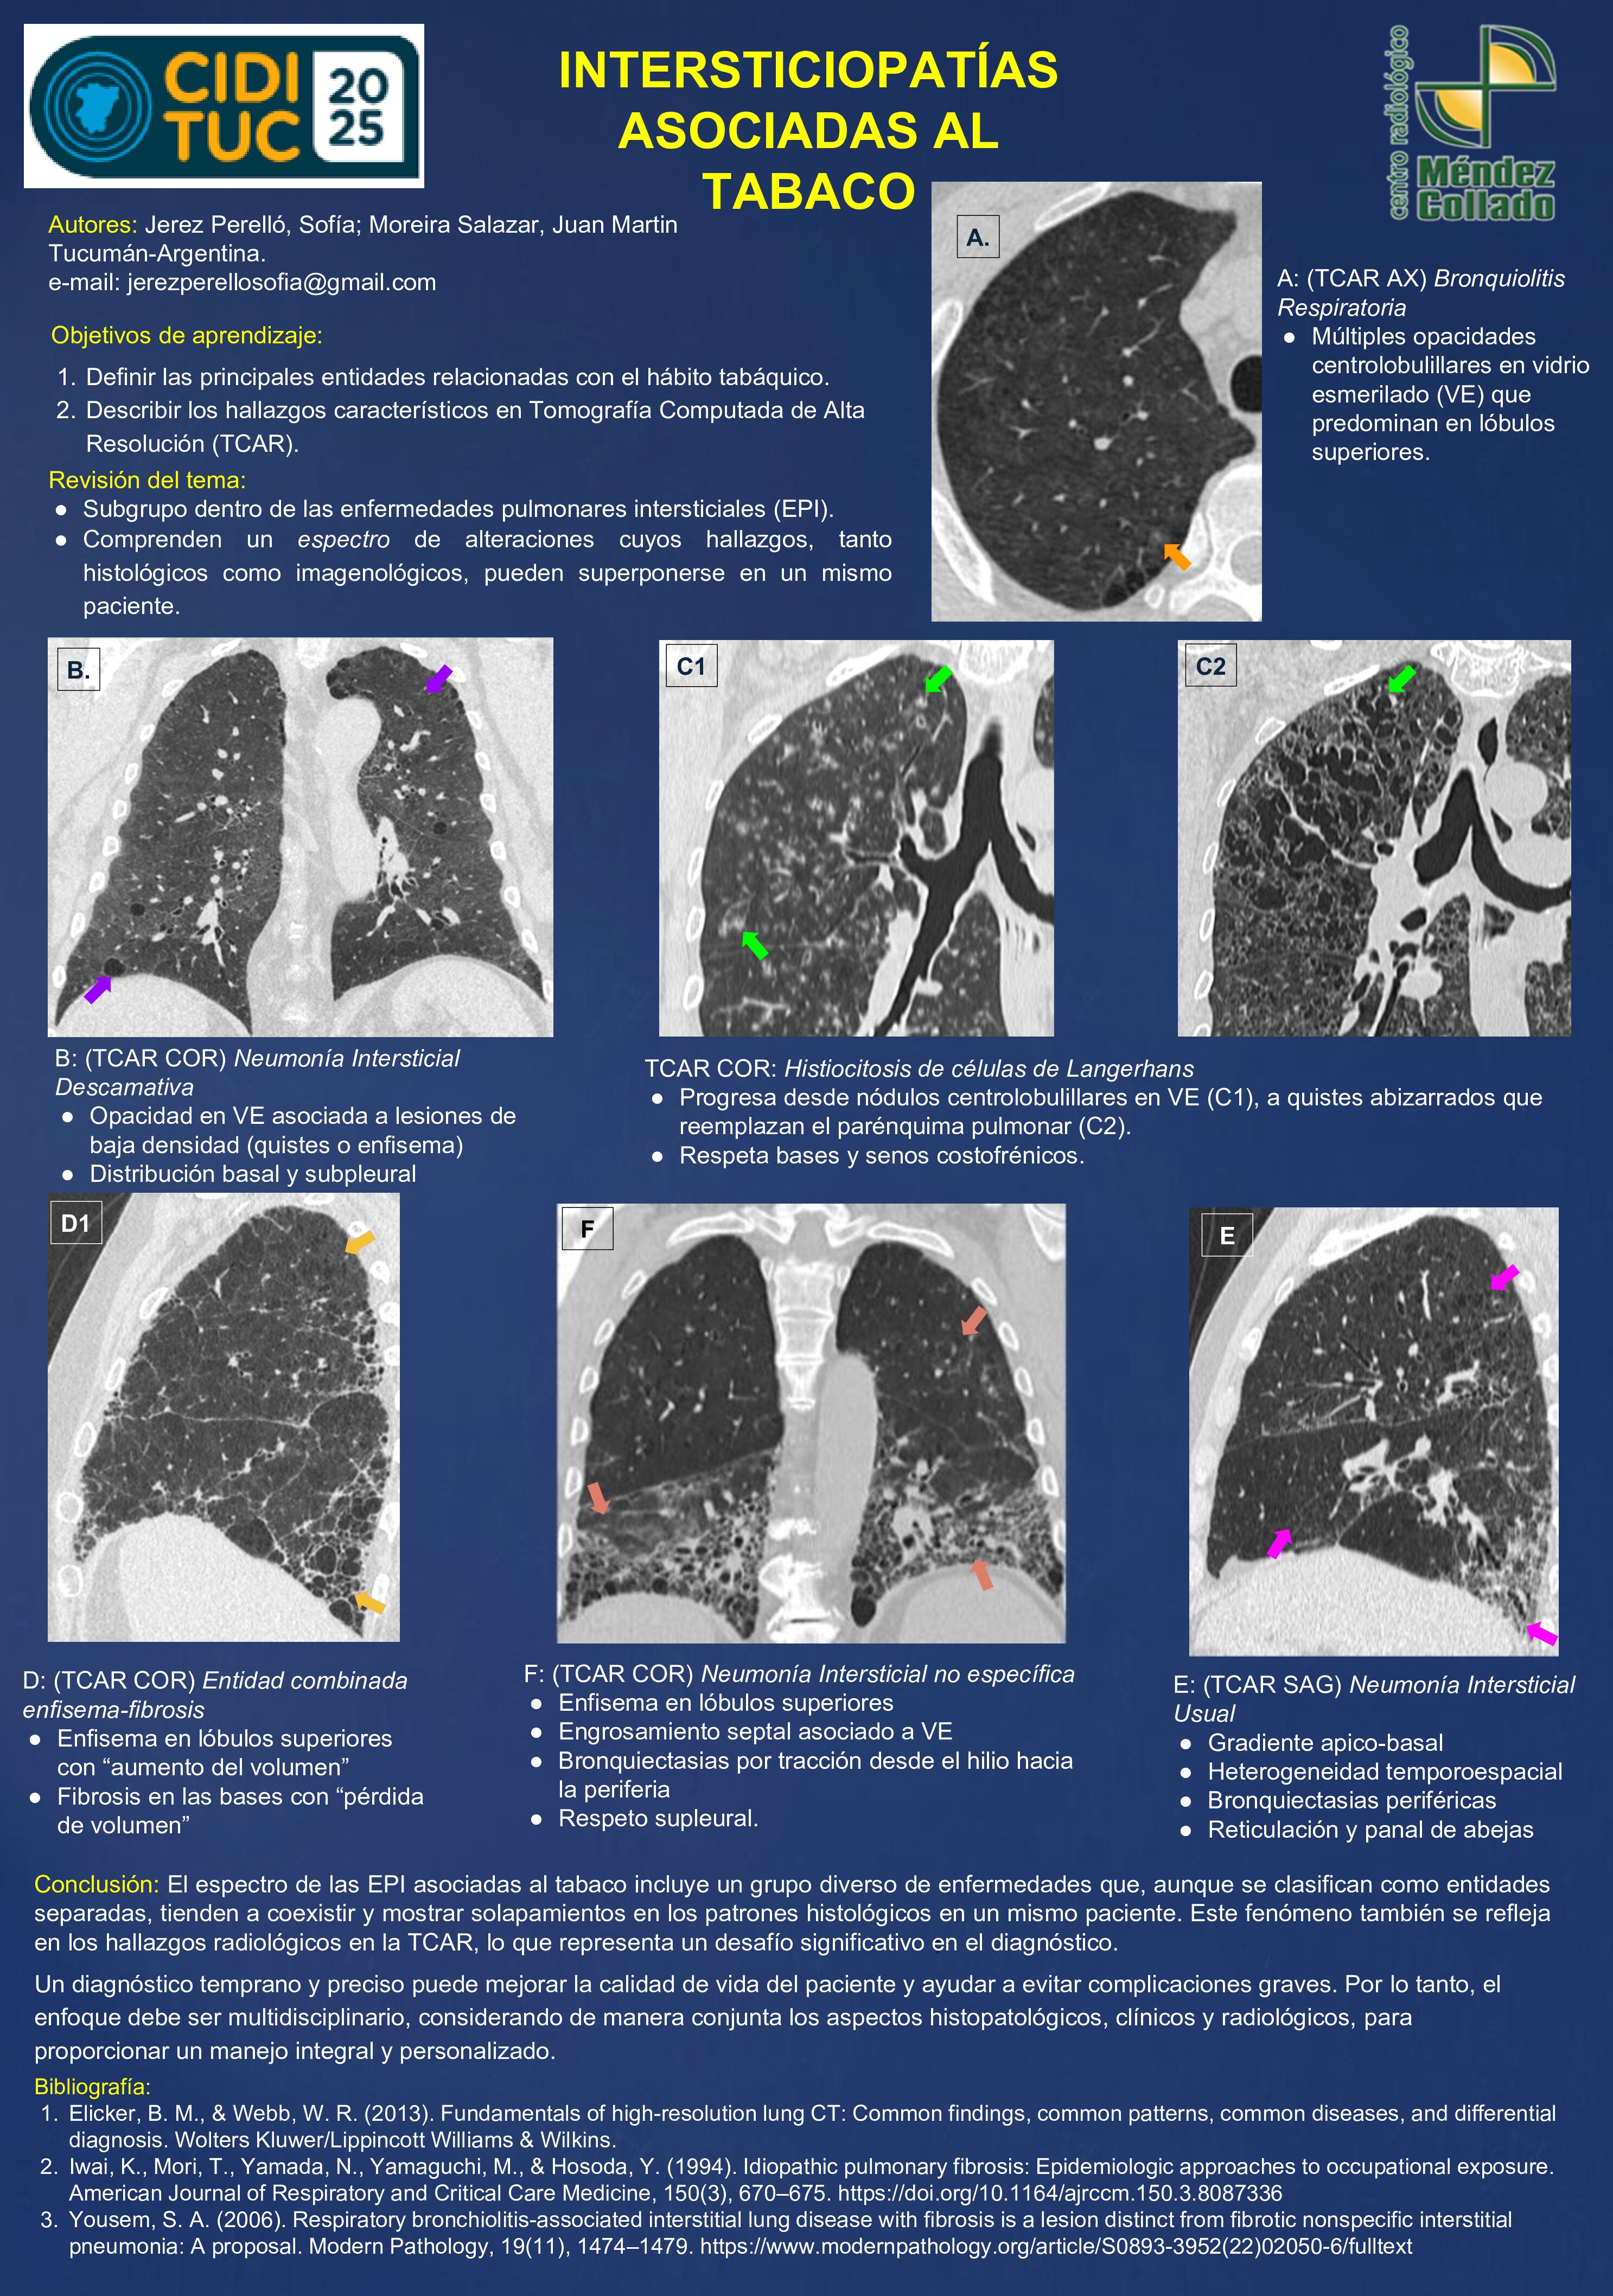

INTERSTICIOPATÍAS ASOCIADAS AL TABACO

23/07/2025